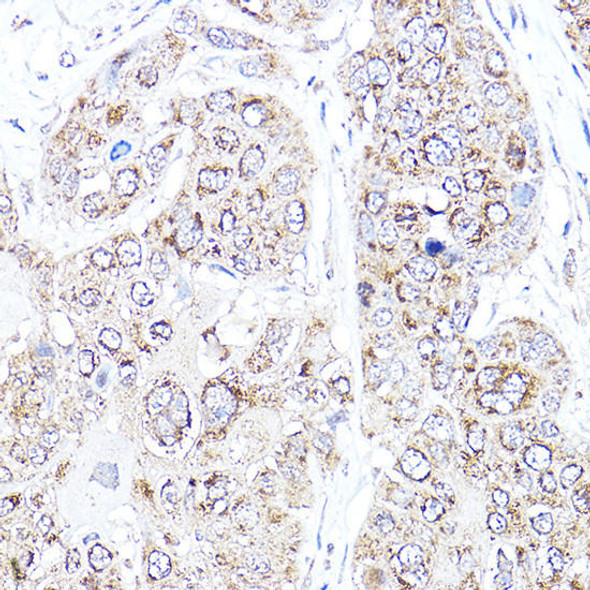

MCM4 Rabbit Polyclonal Antibody (CAB13513)

MSRP:

Now:

€96 - €370

Was: